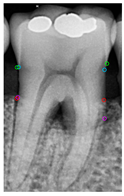

2.6.1. Retained the Largest Mask

Three different mask categories are obtained from the Mask R-CNN prediction results: Tooth Mask, Bone Mask, and Crown Mask. After acquiring these masks, only the fully segmented teeth are analyzed. For the incomplete teeth within the Tooth Mask, the neighboring Tooth Mask needs to be addressed. Since YOLOv8 was used earlier to extract individual teeth, each Tooth Mask contains one complete tooth, covering most of the area, allowing the removal of the masks of any incomplete teeth, as shown in Figure 7a,b.

Figure 7.

Mask R-CNN predictions for single tooth and Tooth Mask processing. (a) Mask R-CNN prediction. (b) The mask predicts the result. (c) Removing incomplete Tooth Mask.

Instance segmentation not only requires detecting the object’s class and location but also involves pixel-level segmentation for each object, each object is segmented into a unique region, even if they belong to the same class. The study identifies all pixel values within the Tooth Mask and saves the masks predicted by Mask R-CNN, representing the pixels of the same object with the same value. The number of different pixel values is then calculated and the pixel value with the largest area is recorded. Other objects with different pixel values are removed, as shown in Figure 7c. This method ensures that only the complete Tooth Mask is used for analysis, thereby improving diagnostic accuracy and efficiency.